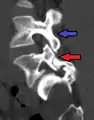

Anterolisthesis L5/S1. Blue arrow normal pars interarticularis. Red arrow is a break in pars interarticularis.